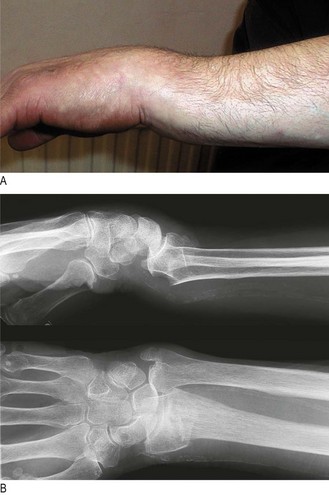

Osteoporosis is systemic skeletal loss of bone mineral density with associated microarchitectural deterioration. It is the most common cause of abnormal bone structure. The incidence increases with age, particularly in postmenopausal women (Box 14.27). In the absence of complications, osteoporosis is asymptomatic. Although any osteoporotic bone can fracture, common sites are the distal radius (Fig. 14.56), neck of femur (Fig. 14.43), proximal humerus and the spinal vertebrae. Caucasians in Europe have a lifetime risk of osteoporotic fracture of 50% in women and 20% in men.

Fig. 14.56 Colles’ fracture. (A) Clinical appearance of dinner fork deformity. (B) X-ray appearance.